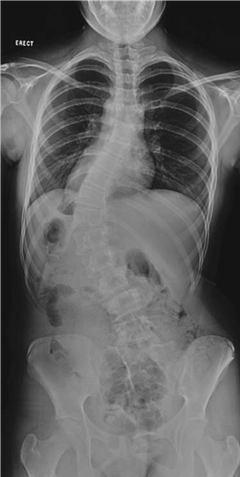

๐ŸŽ“ Viva 73

Illustration 22 for Ace FRCS Orthopaedics: Oxford University Press Adult Pathology Viva

๐Ÿ” Click to enlarge

Clinical Radiograph / Orthopedic Image

What is the name of the spinal deformity in the photograph above?

At what age and in which sex does it most commonly present?

What factors affect progression of the deformity?

How is it classified?

This is idiopathic scoliosis.

I t is commonest in girls and often presents around adolescence. The thoracic curve is usually right sided. The prevalence is around 3 % of the population, although less than 10 % of curves need treatment.

What factors aff ect progression of the deformity?

1 . The future growth potential of the patient, i.e. the level of skeletal maturity at the time of diagnosis. This is measured by the Risser stage: z Risser 0 = no ossification of the iliac epiphysis z Risser 1 = 0โ€“25 % ossification z Risser 2 = 25โ€“50 % ossification z Risser 3 = 50โ€“75 % ossification z Risser 4 = 75โ€“100 % ossification z Risser 5 = fused epiphysis

2. The curve magnitude at the time of diagnosis:

z Curves of <30 ยฐ at maturity are unlikely to progress z Curves of 30โ€“50 ยฐ at maturity are likely to progress another 10โ€“15 ยฐ z Curves of > 50 ยฐ at maturity are likely to progress at around 1 ยฐ /year

3. Sex: curves in females are more likely to progress 4. Curve type: double curves are more likely to progress

How is it classifi ed?

There are two common classifi cation systems.

King and Moe describe Types 1โ€“5 depending on the shape of the curve:

z Type1: S-shaped double curve where the lumbar curve is larger or less flexible z Type 2: S-shaped double curve where the thoracic curve is larger or less flexible z Type 3: single thoracic curves z Type 4: long thoracic curves where L4 is tilted into the curve z Type 5: double thoracic curve where T1 is tilted into the thoracic curve

The more complex Lemke classifi cation system describes the curve type (1โ€“6) and adds a modifi er (A, B, or C) depending on where the lumbar curve is in relation to central sacral vertical line, and another modifi er (โ€“, N, or + ) based on the thoracic sagittal profi le.